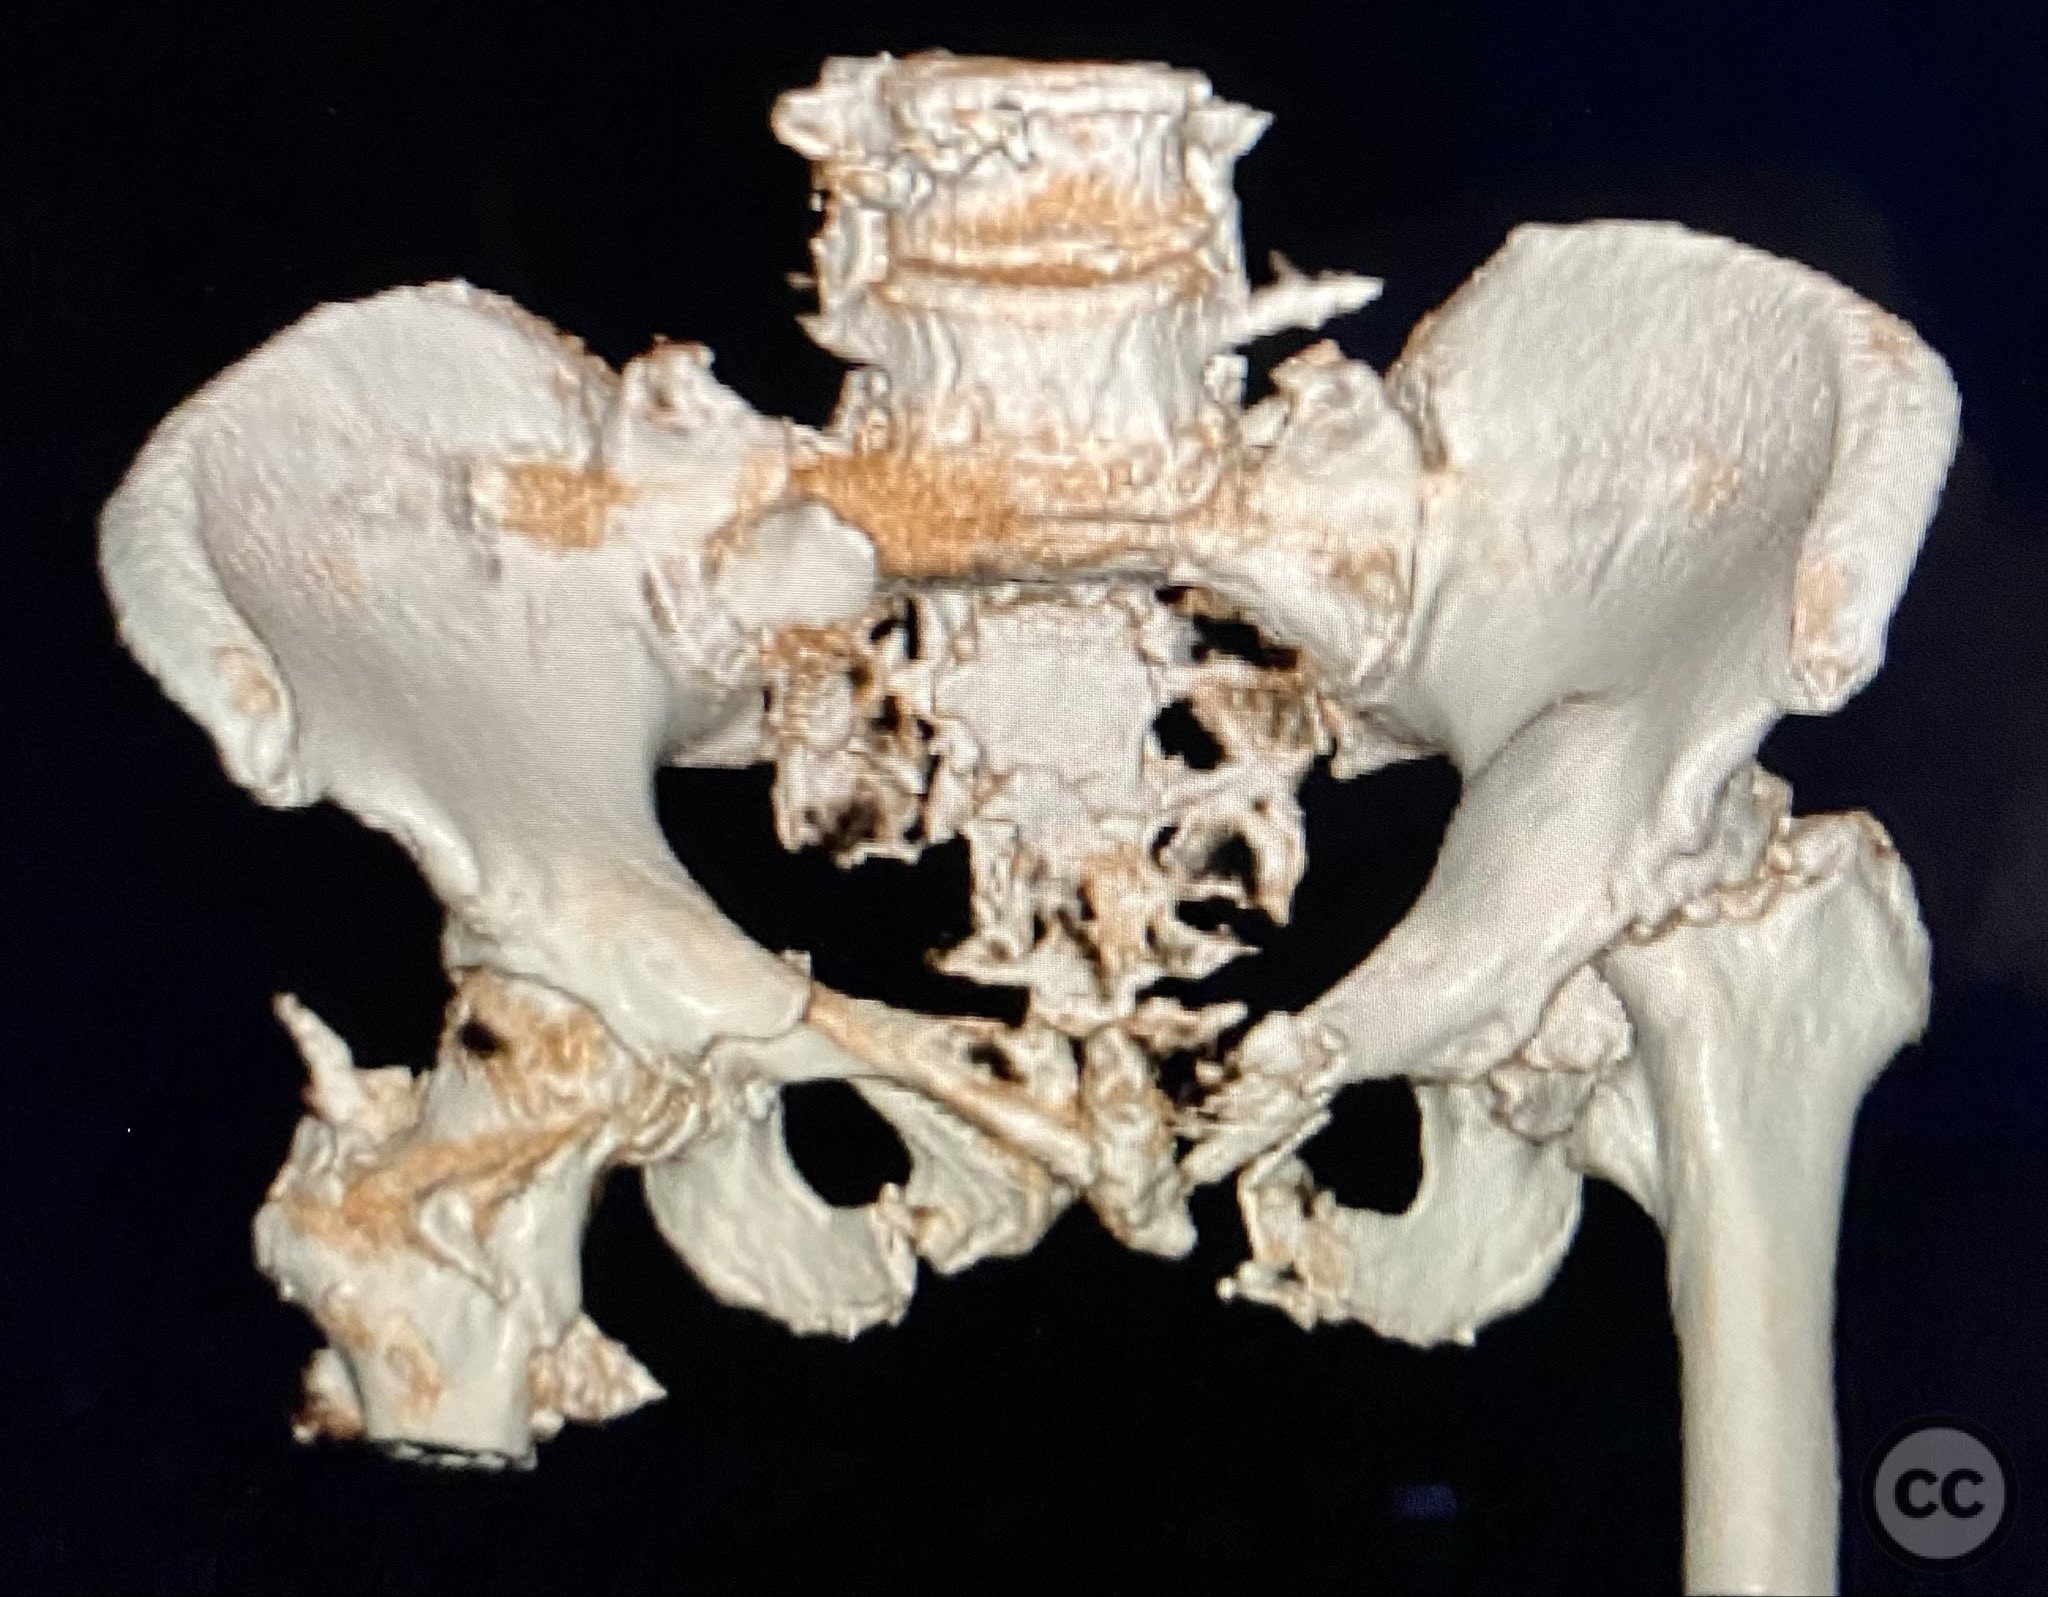

Clinical and radiological findings:  An elderly patient sustained multiple traumatic injuries, including complex unstable pelvic ring disruption (AO/OTA 61-C, likely C1 or C2 based on instability and comminution), comminuted proximal femoral fracture (AO/OTA 31-A3 or 31-B, depending on trochanteric or neck involvement), and significant abdominal trauma necessitating intra-abdominal packing. Initial clinical evaluation revealed hemodynamic instability and poor bone quality consistent with advanced age. Distal femoral traction was applied for provisional reduction. Radiological assessment was limited by osteopenia, fracture comminution, and the presence of abdominal packing materials.

Planning remarks:  The preoperative plan included early closed reduction maneuvers under fluoroscopic guidance, percutaneous stabilization of the pelvic ring with cannulated screws, and intramedullary nailing of the proximal femur. The anatomical approach for pelvic fixation was percutaneous iliosacral screw placement; for the femur, a standard antegrade intramedullary nailing technique was planned.

Anatomical surgical approach:  Percutaneous iliosacral screw fixation was performed through small lateral gluteal incisions, with blunt dissection to the outer table of the os ilium. Under fluoroscopic guidance, guidewires were advanced across the sacroiliac joint into the S1 body, followed by cannulated screw insertion. For the proximal femur, a longitudinal incision was made proximal to the greater trochanter, splitting the fascia lata and gluteus medius fibers to access the piriformis fossa. A guidewire was inserted into the medullary canal, followed by sequential reaming and insertion of an intramedullary nail.

Intraoperative imaging was challenging due to osteopenic bone, fracture comminution, and interference from abdominal packing. Accurate identification of safe osseous corridors for iliosacral screw placement required multiple fluoroscopic projections and careful attention to pelvic landmarks. Bone quality necessitated cautious screw advancement to avoid iatrogenic cortical breach. After pelvic fixation, intramedullary nailing of the proximal femur proceeded without complication. Abdominal packing was removed and laparotomy wound closed after skeletal stabilization. Early mechanical stabilization of both pelvic and femoral injuries was prioritized to optimize survivability in this multiply injured elderly patient.